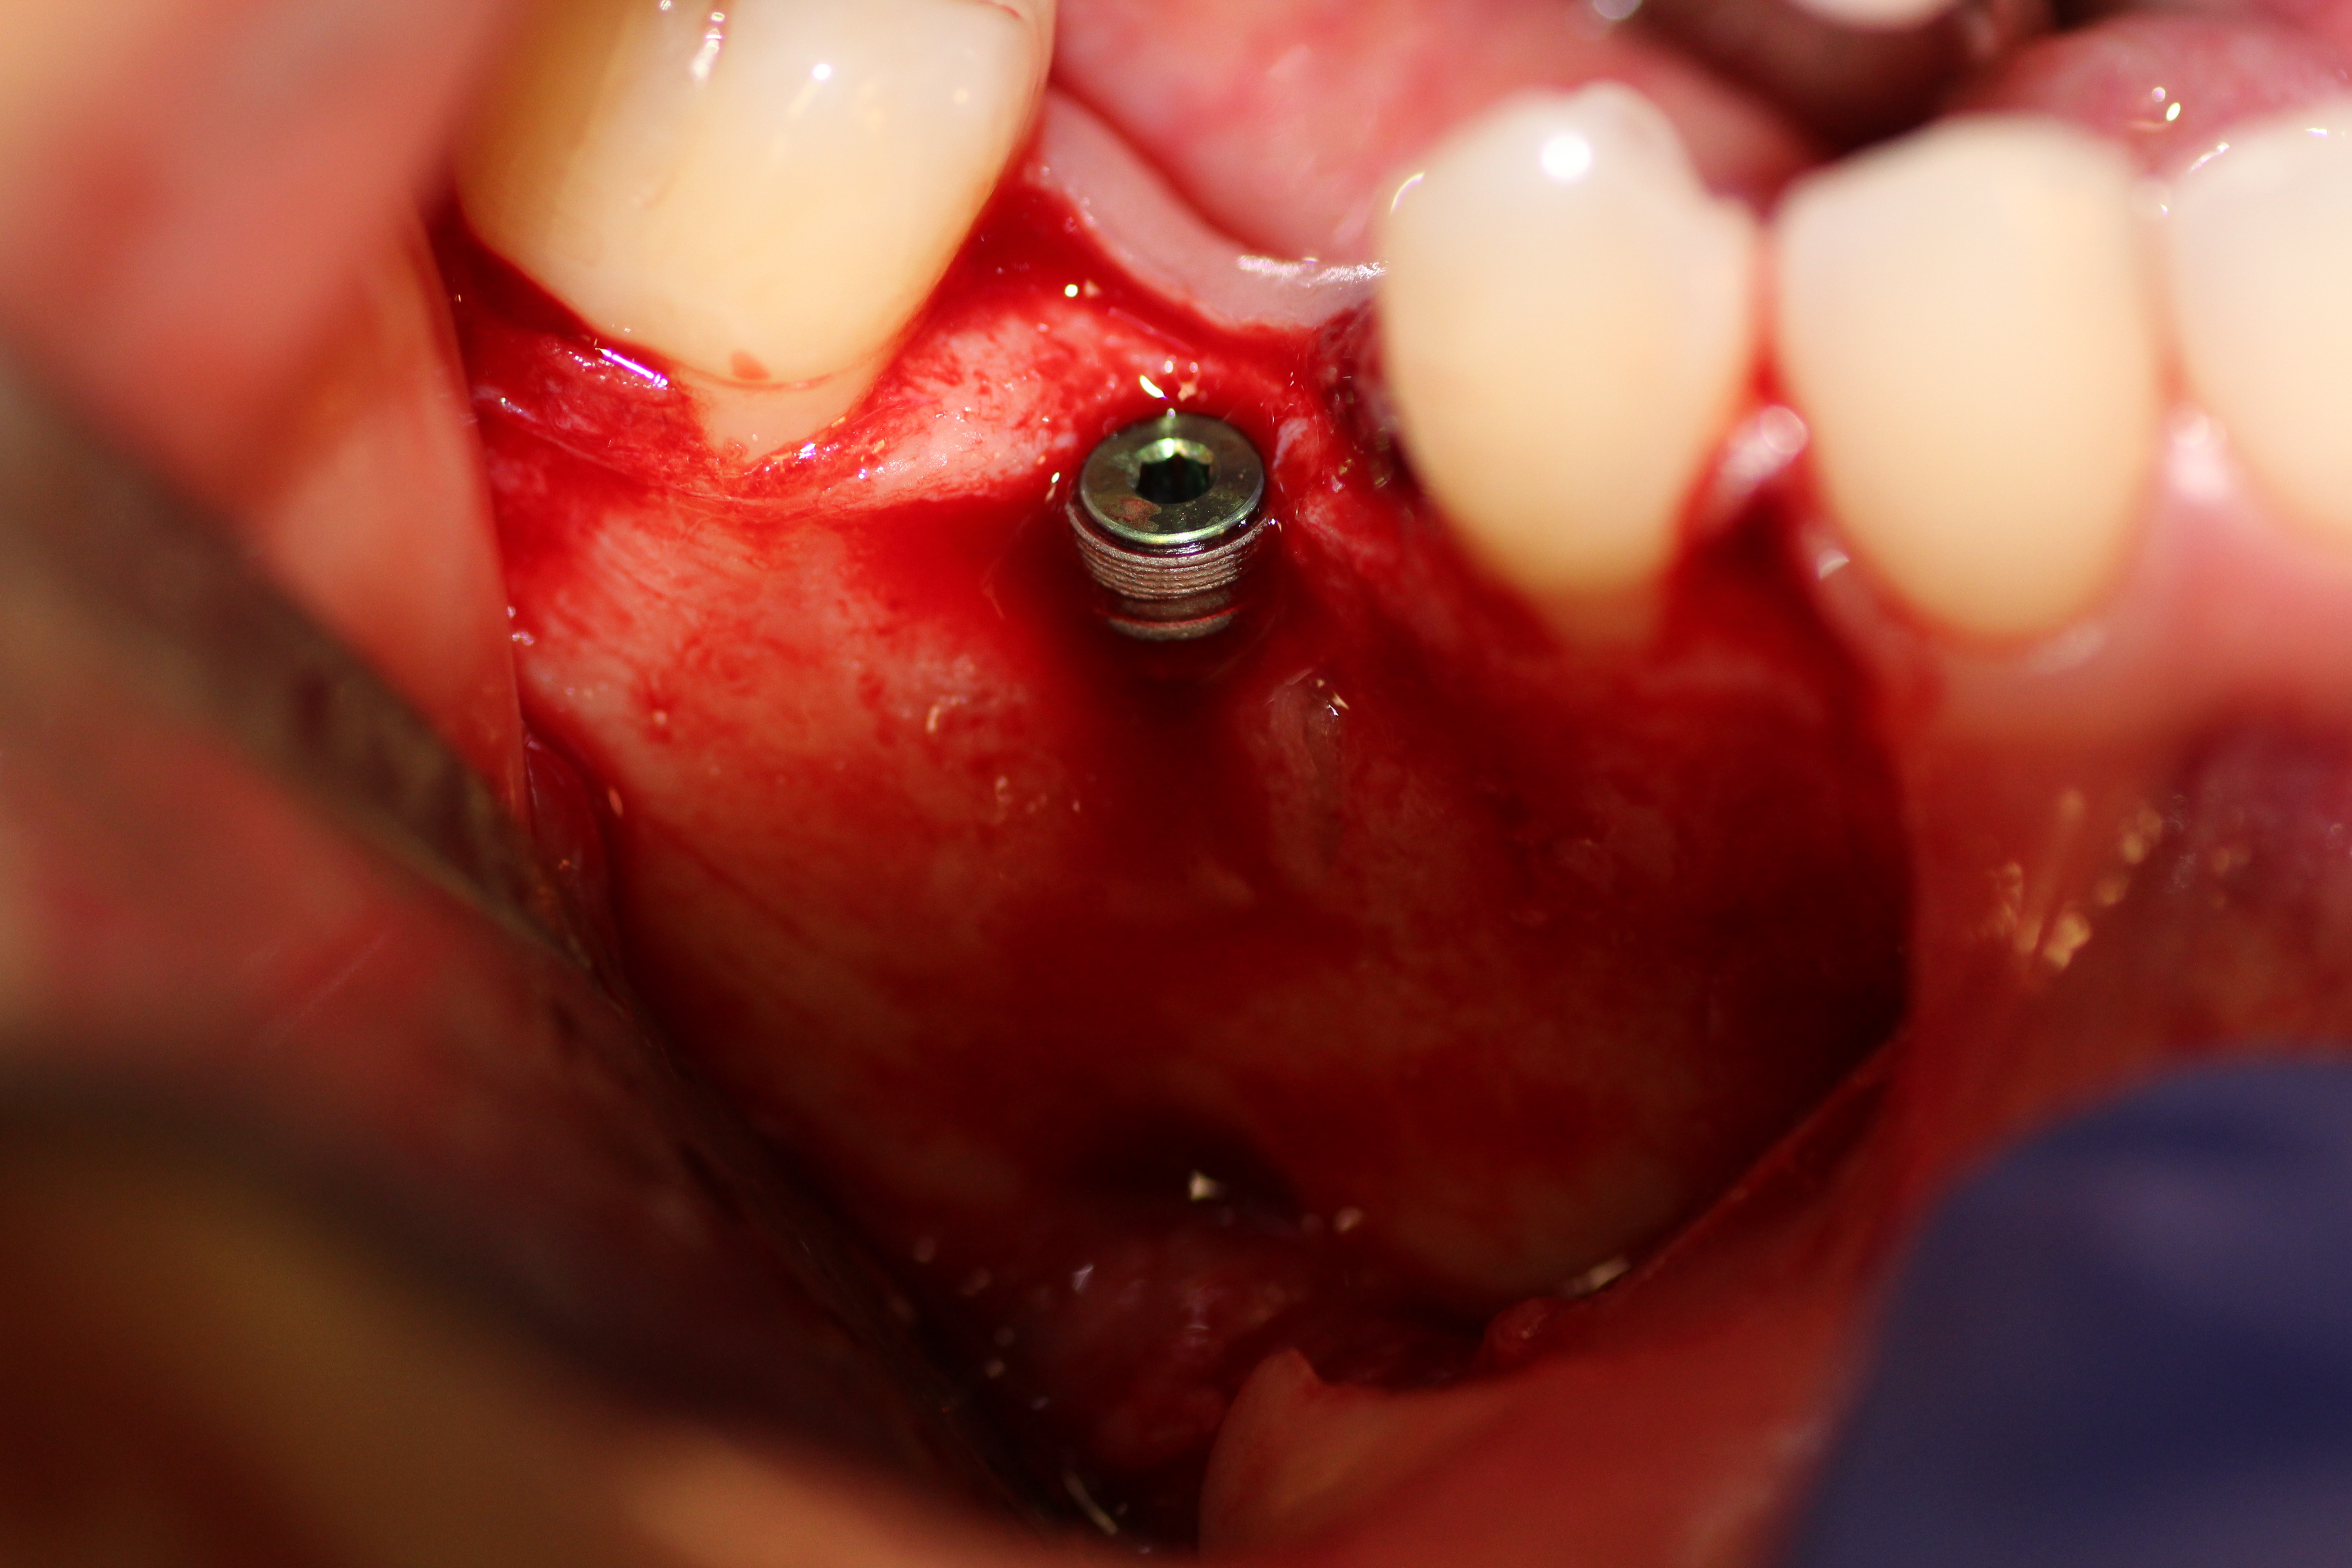

Case #2

Extraction and immediate implant placement with guided bone regeneration.

- Implant is in place.

- Bony defect measuring 3mm x 10 mm.